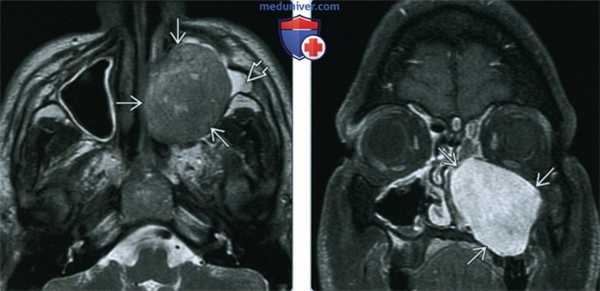

(Слева) При аксиальной МРТ Т2 у юного пациента мужского пола с отеком лица и обструкцией носовой полости в левой верхнечелюстной пазухе визуализируется хорошо отграниченное гипоинтенсивное образование, снаружи отчего виден «запертый» секрет.

(Справа) При корональной МРТ Т1 С+ FS визуализируется нейрофиброма, диффузно накапливающая контраст. Контрастное усиление позволяет легко отличить солидную опухоль от мукоцеле, - более типичной экспансивной патологии околоносовых пазух.